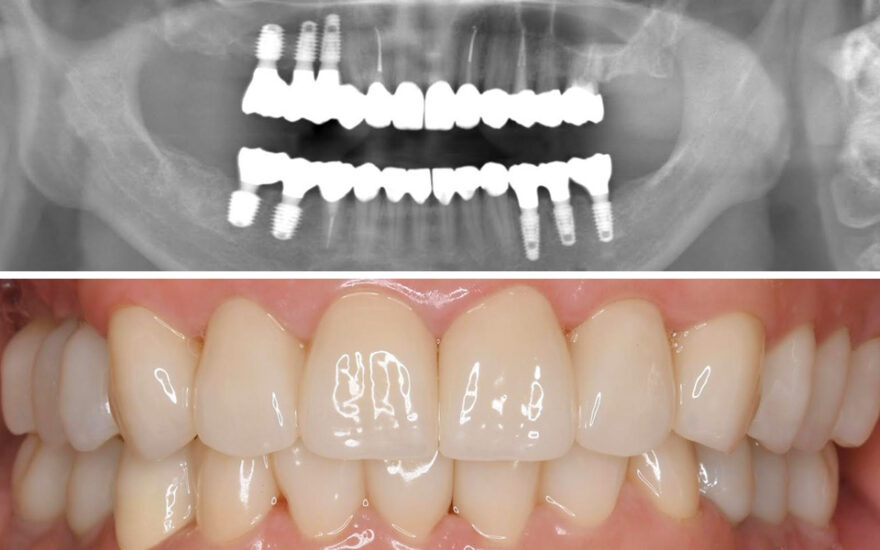

石山先生が製作したインプラント上部構造(セラミック歯)の治療例

治療中の口腔内写真

治療後のレントゲン写真

治療後の口腔内写真

患者様は30代女性、治療期間は3ヶ月。

この症例の治療費

前歯プレミアムインプラント2本→1本あたり495,000円(税込)

総額990,000円(税込)

この症例のリスク

インプラントが稀に脱落することがあります。

その場合は10年保証が付いていますので、速やかに無料対応をさせて頂きます。